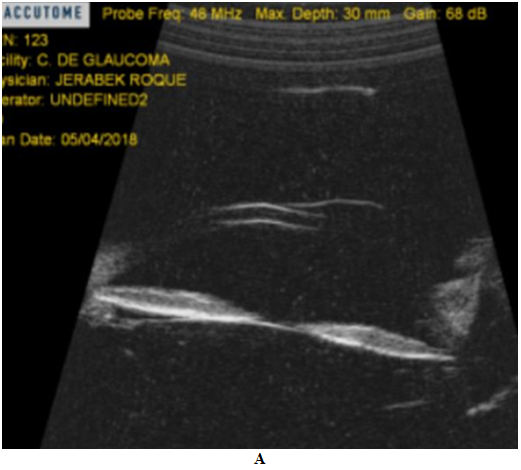

Pseudoexfoliation syndrome may be associated with iris translumination defects, increased pigmentation of the patchy type TM by 50%, usually unilateral, and elevated IOP. However, the patient did not present deposits of pseudoexfoliation, nor transillumination defects of the iris and the angular pigment dispersion was homogeneous and occupied 360° and was bilateral.7,12 The presence of a pigmented intraocular tumor was also ruled out by gonioscopy and UBM, where it was also possible to appreciate a posterior concavity of the iris and an intimate iridozonular contact.1,7,9

Figure 9 Ultrabiomicroscopy shows posterior concavity of the iris and greater iridozonular contact in BE, rest of the structures S/P.